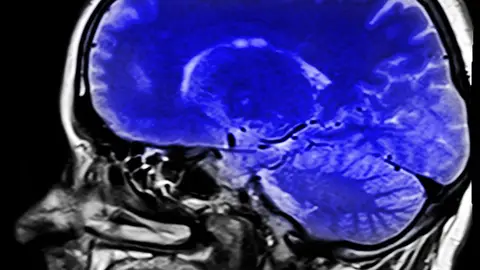

La conciencia es la base del ser humano. Representa el ser y la unión del hombre con el universo. Y al igual que el cosmos tiene materia oscura, el cuerpo humano también tiene materia oscura.